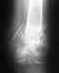

Вот что в итоге получилось, снимки от 13 января 2010 года. В феврале убрали пластину, т.к. были боли в ноге в определенных ситуациях, например, при беге. Хотелось бы, если Вам не сложно, услышать оценку оставшейся деформации,насколько это критично в будущем (сейчас вроде всё ОК). Наверное, пора бы уже и позабыть, но всё ж терзают смутные сомнения, правильно я поступил, что не стал переделывать...Спасибо заранее.

Кликните для загрузки файла 1.jpg

39KB (40508 bytes)